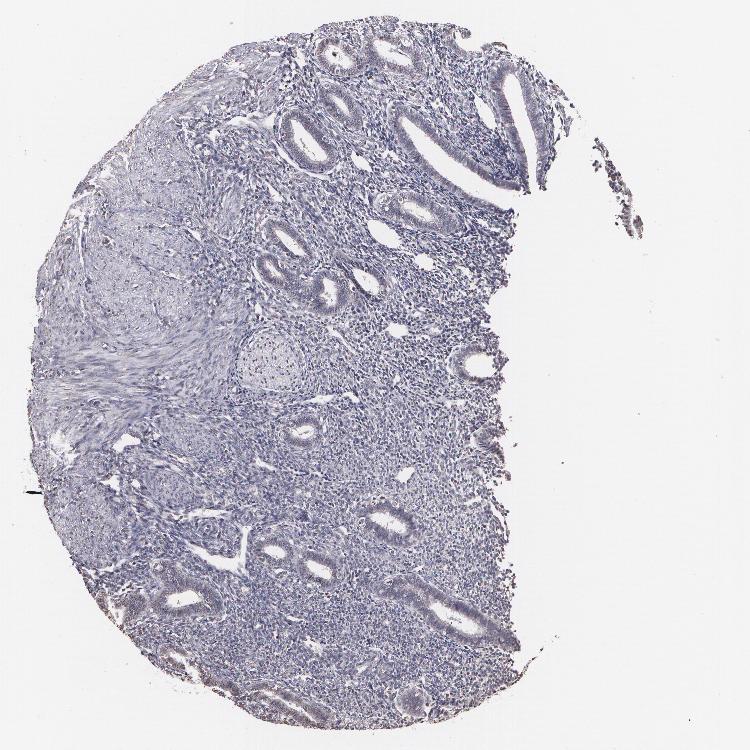

ENDOMETRIUM 1 - Antibody stainingi

Antibody staining in the annotated cell types in the current human tissue is reported as not detected, low, medium, or high, based on conventional immunohistochemistry profiling in selected tissues. This score is based on the combination of the staining intensity and fraction of stained cells.

Each image is clickable and will lead to virtual microscopy that enables deeper exploration of all samples and also displays staining intensity scores, fraction scores and subcellular localization as well as patient and tissue information for each sample.

Antibody CAB002008Antibody CAB002009

Cells in endometrial stroma Not detectedLow

Glandular cells Not detectedLow